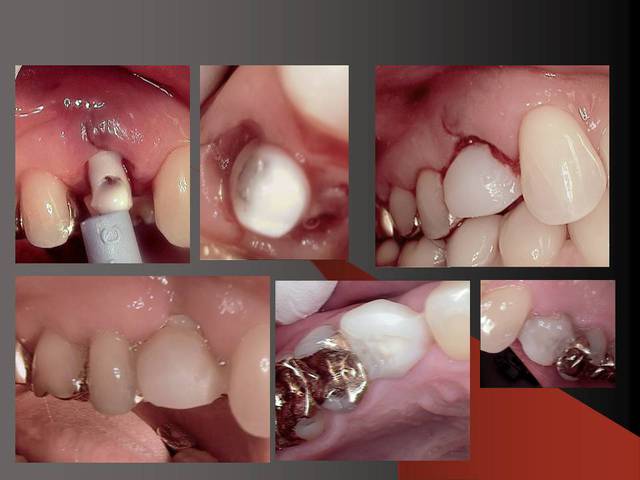

Le dernier photo cela montre le système des Prep Caps :

il y a deux point de réferences en rouge c´est où finit la prep caps et en jaune où commence la prep caps (à la base) .

Merci pour ta remarque.C´est vrai que cela est mieux si on ne prérare pas ou presque pas les prep cap à cause des shippings . Normalement je ne les prépare pas, je choisis une forme (avec angle et longueur diiférents) selon le cas et ensuite je les cémente.

Sur la photo 5 on voit que je prépare surtout le titane de l´implant, le titane ne donne pas beaucoup du chaud quand il est préparé avec l´eau (pas comme aluminium par exemple).